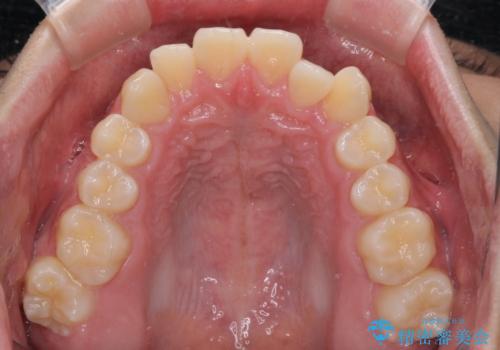

受け口傾向の骨格であり、前歯はクロスバイトまたは切端咬合となっており、叢生は警備であったため、下顎を中心に歯列全体の後方移動を行い、IPR(歯と歯の間を削る)によってデコボコが解消するように設計し、インビザラインにより治療を行うこととしました。

受け口傾向のインビザライン矯正は比較的治療を行いやすいため、きれいに仕上げることができました。舌の突出癖が顕著であったため、改善のためのトレーニングをしっかりと行っていただきました。